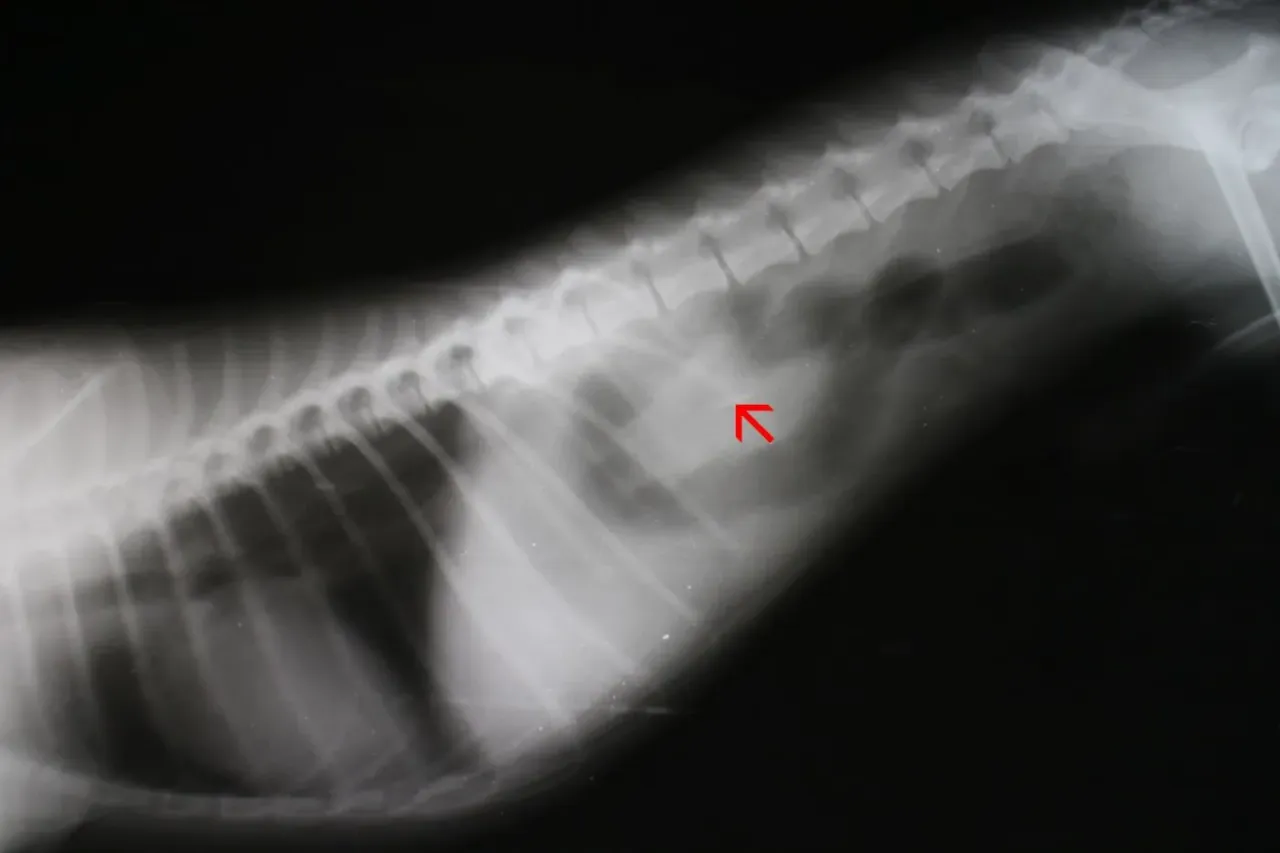

Od palpacji po RTG i USG: Jak lekarz znajduje problem w jelitach?

Pierwszym krokiem będzie zawsze szczegółowy wywiad z Tobą. Przygotuj się na pytania o to, co pies mógł połknąć, kiedy to nastąpiło, jakie objawy zauważyłeś i od kiedy. Każda informacja jest na wagę złota! Następnie lekarz przeprowadzi badanie kliniczne, w tym delikatną palpacyjną ocenę brzucha, aby sprawdzić, czy jest bolesny, napięty lub wzdęty.

Kluczowe w diagnostyce są badania obrazowe:

- RTG (rentgen): Jest bardzo skuteczny w wykrywaniu przedmiotów metalowych, kości, kamieni. Niestety, nie wszystkie ciała obce są widoczne na zdjęciu rentgenowskim.

- USG (ultrasonografia): Jest pomocne w wizualizacji przedmiotów niewidocznych na RTG, takich jak te wykonane z plastiku, tkanin czy drewna. Może również pomóc ocenić stan ścian jelit i obecność płynu w jamie brzusznej.

- W niektórych przypadkach stosuje się RTG z kontrastem, gdzie podaje się psu specjalny środek, który pozwala na obserwację jego przepływu przez przewód pokarmowy i uwidocznienie ewentualnych blokad.